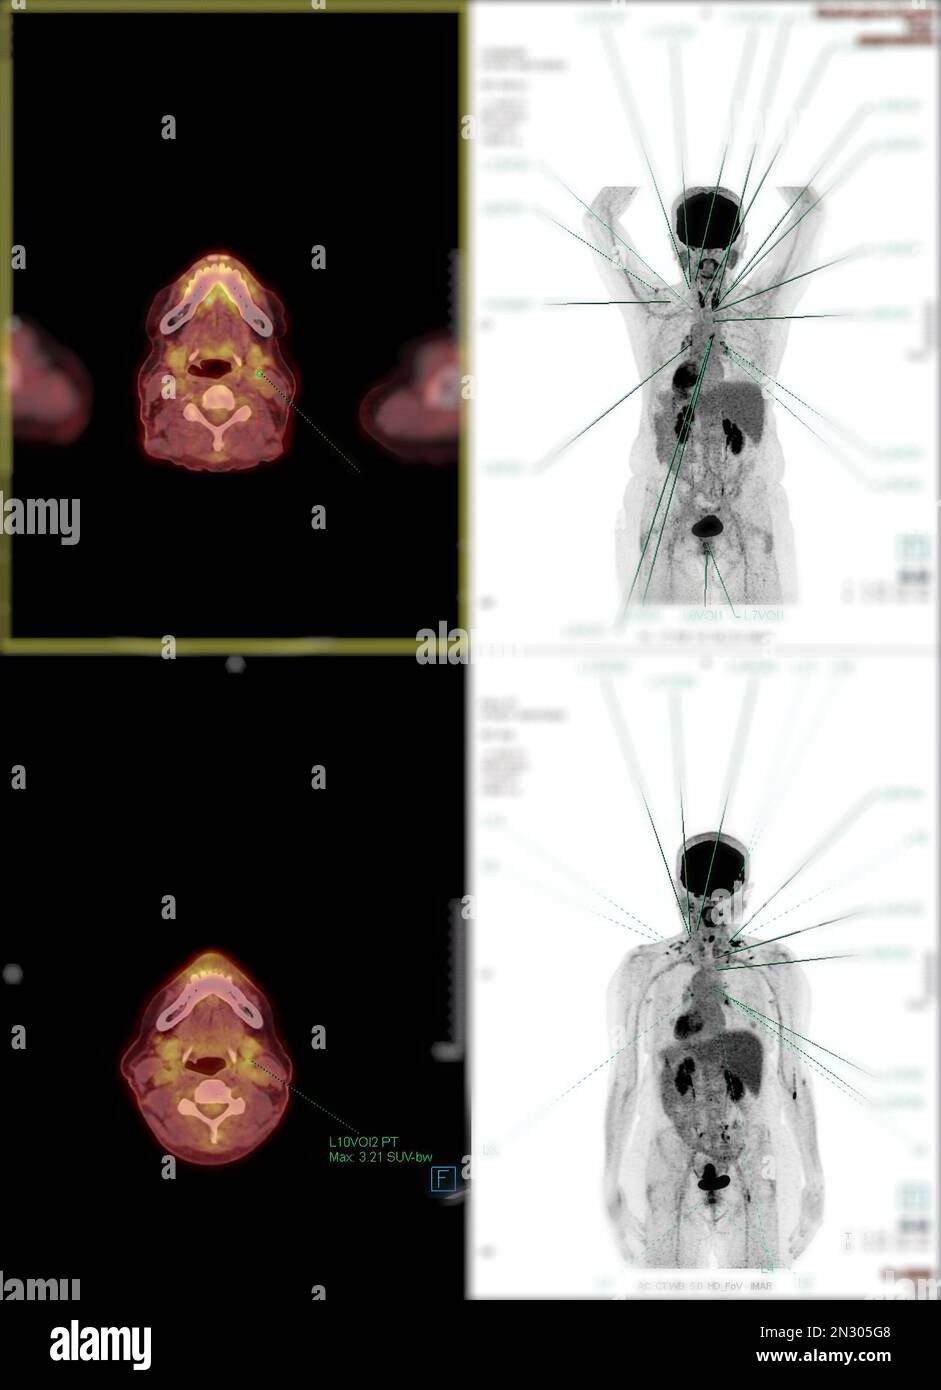

RF2N305G8–La tomographie par émission de positrons (TEP) CT scan utilise un médicament radioactif (traceur) pour montrer l'activité métabolique normale et anormale de tout le corps humain

RF2N305M5–La tomographie par émission de positrons (TEP) CT scan utilise un médicament radioactif (traceur) pour montrer l'activité métabolique normale et anormale de tout le corps humain